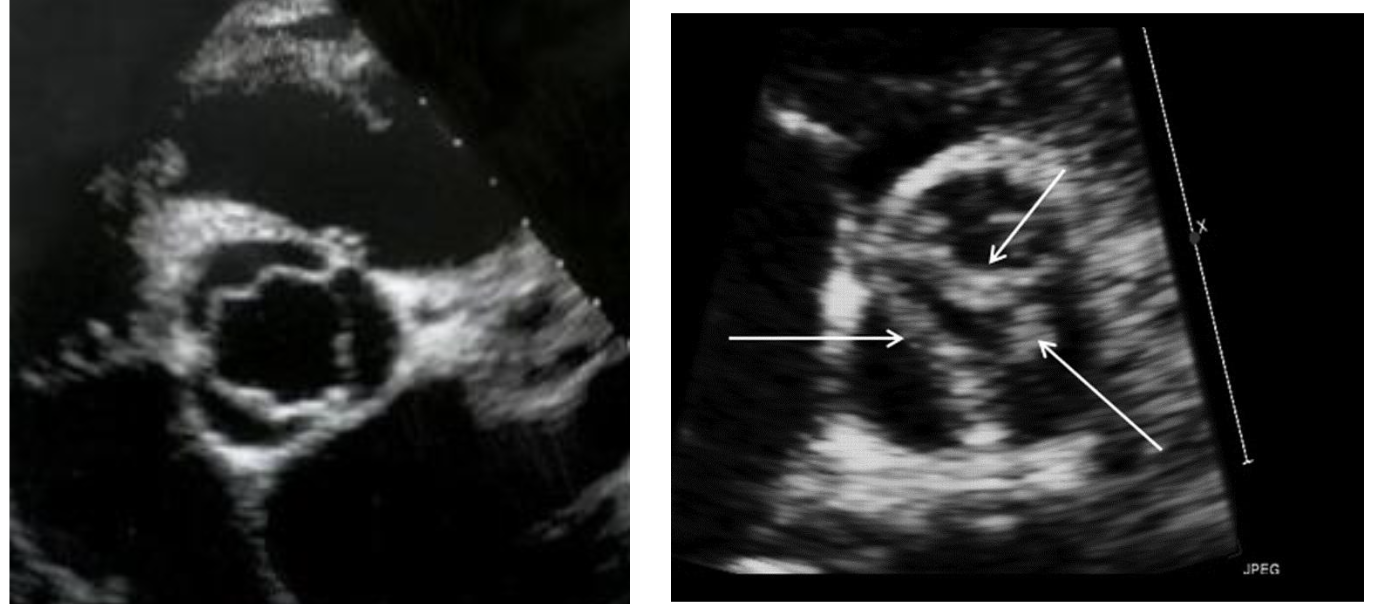

What are the 2 types of congenital bicuspid aortic valves

Without a raphe

rare

cusps usually equal in size

With a raphe (seam/union)

common

most common location of raphe is between the RCC and LCC

cusps unequal in size